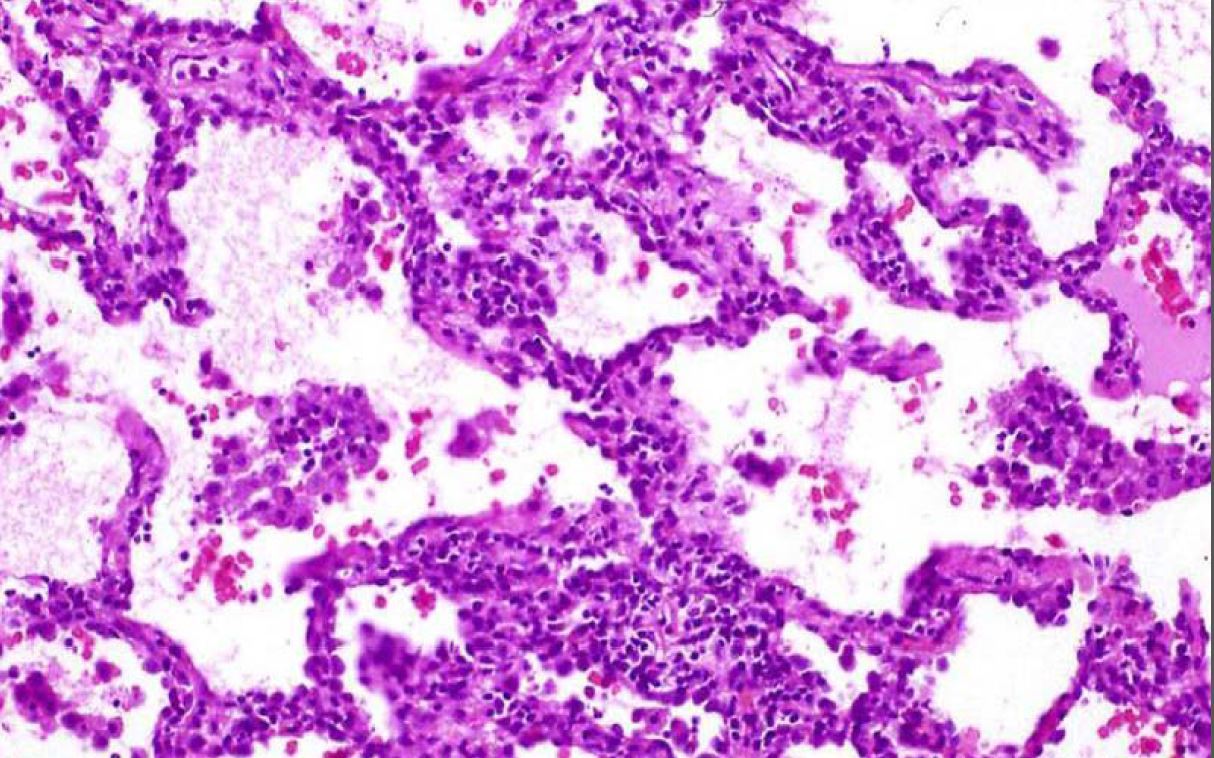

Name this entity.

Organizing diffuse alveolar damage

notice hyaline membrane